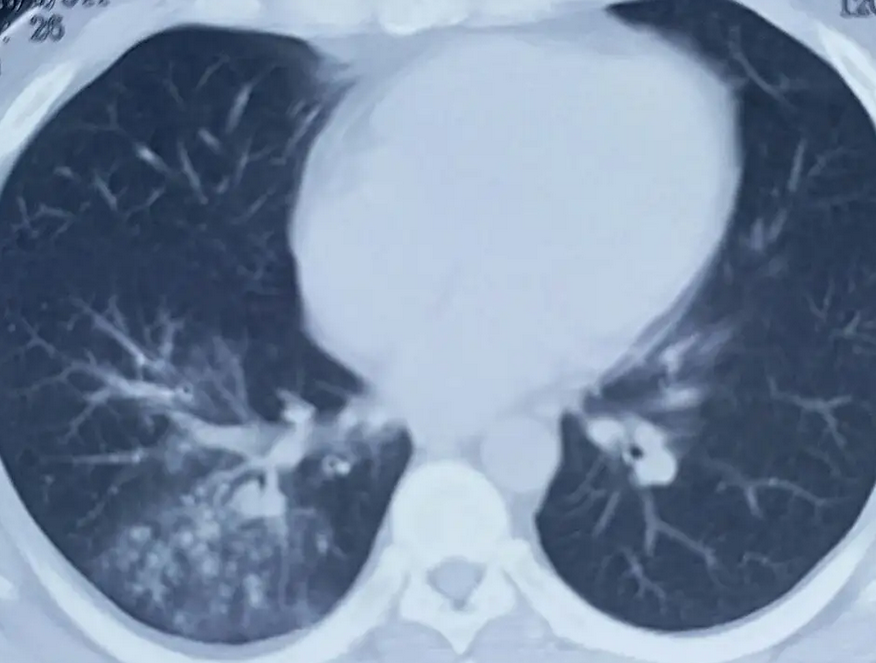

近日,支原体肺炎频繁,特别是在中小学生中比较流行,也有新闻爆料小学生打着吊瓶写作业,江苏南通一名8岁男孩因患肺炎支原体肺炎,被家人送到医院住院,就在入院治疗的第三天凌晨,小男孩突然被诊断为脑干梗死,目前通过手术治疗已经脱离危险。